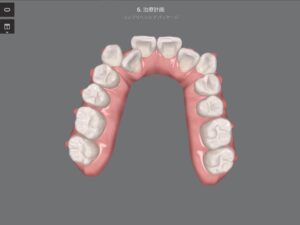

・私の歯並びの変化

上が矯正開始前、下が現在の状態です。

正面から見ても歯が動いてるようには見えませんが、咬合面(歯の噛む面)から確認すると、奥歯のあたりに隙間ができています!

クリンチェックと比較してみると、同じところに隙間ができているので、順調に進んでいるのが確認できます。

このように写真で見ると、着実に歯が動いているのが確認できてモチベーションが上がりますね!